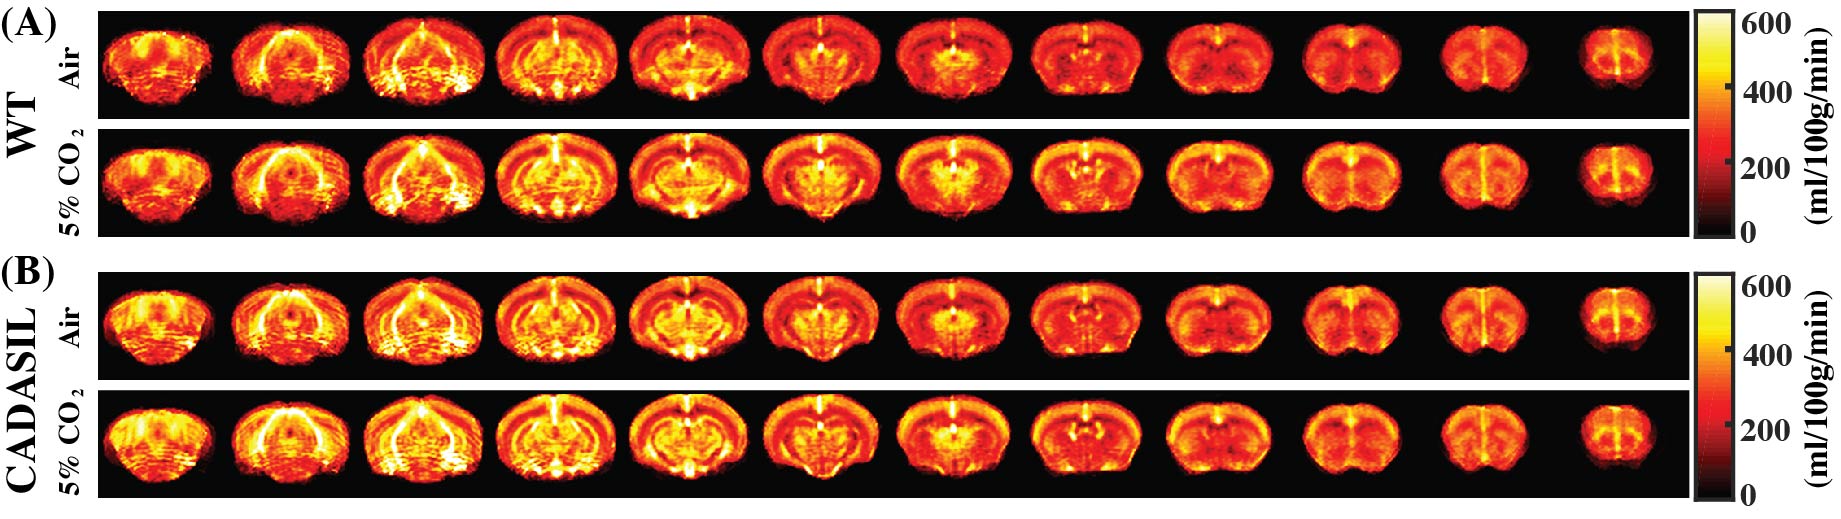

Averaged CBF maps of WT and CADASIL mice under normocapnia and hypercapnia were presented in Fig. 4. CBF increases from normocapnia to hypercapnia can be observed at different brain regions in both mouse groups. However, CVR in the CADASIL mice was dramatically lower than that in the WT mice (Fig. 3E, P=0.043, by -57.1%). Impaired CVR in the CADASIL mice is likely attributed to the developmental deficiency in smooth muscle cells11 as a result of NOTCH3 mutation.

Figure 4. Averaged CBF maps of WT (A) and CADASIL (B) mice under normocapnia (medical air) and hypercapnia (5% CO2) conditions.